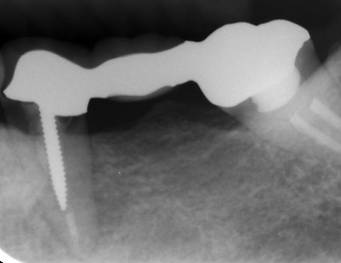

術前パノラマレントゲン写真。根の周りが黒くなり、骨がなくなっていることがわかります

治療後。歯周病で失われた骨が回復しています。使用インプラントはスプラインツイストです。